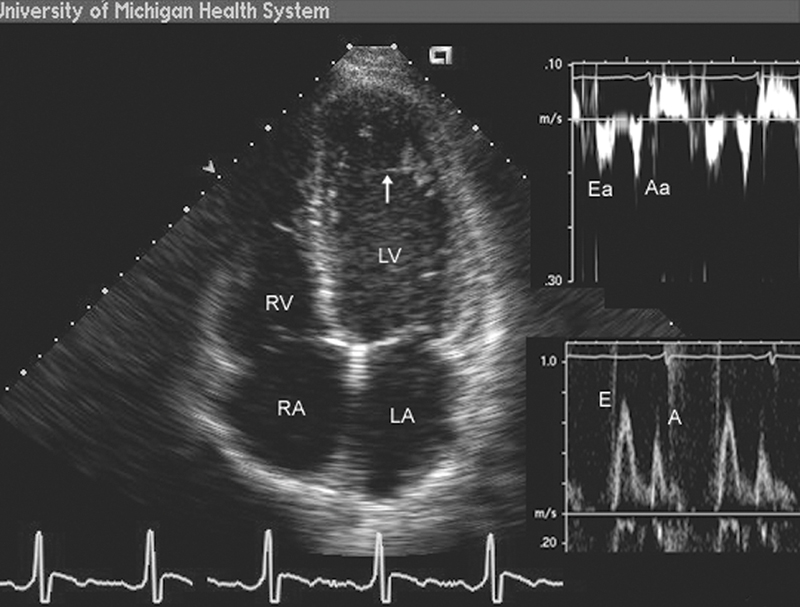

فحوصات تشخيصية لبعض امراض القلب والشرايين التاجية